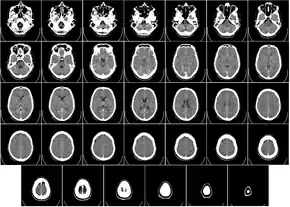

Head

CT scanning of the head is typically used to detect infarction (stroke), tumors, calcifications, haemorrhage, and bone trauma.[32] Of the above, hypodense (dark) structures can indicate edema and infarction, hyperdense (bright) structures indicate calcifications and haemorrhage and bone trauma can be seen as disjunction in bone windows. Tumors can be detected by the swelling and anatomical distortion they cause, or by surrounding edema. CT scanning of the head is also used in CT-guided stereotactic surgery and radiosurgery for treatment of intracranial tumors, arteriovenous malformations, and other surgically treatable conditions using a device known as the N-localizer.[33][34][35][36][37][38]